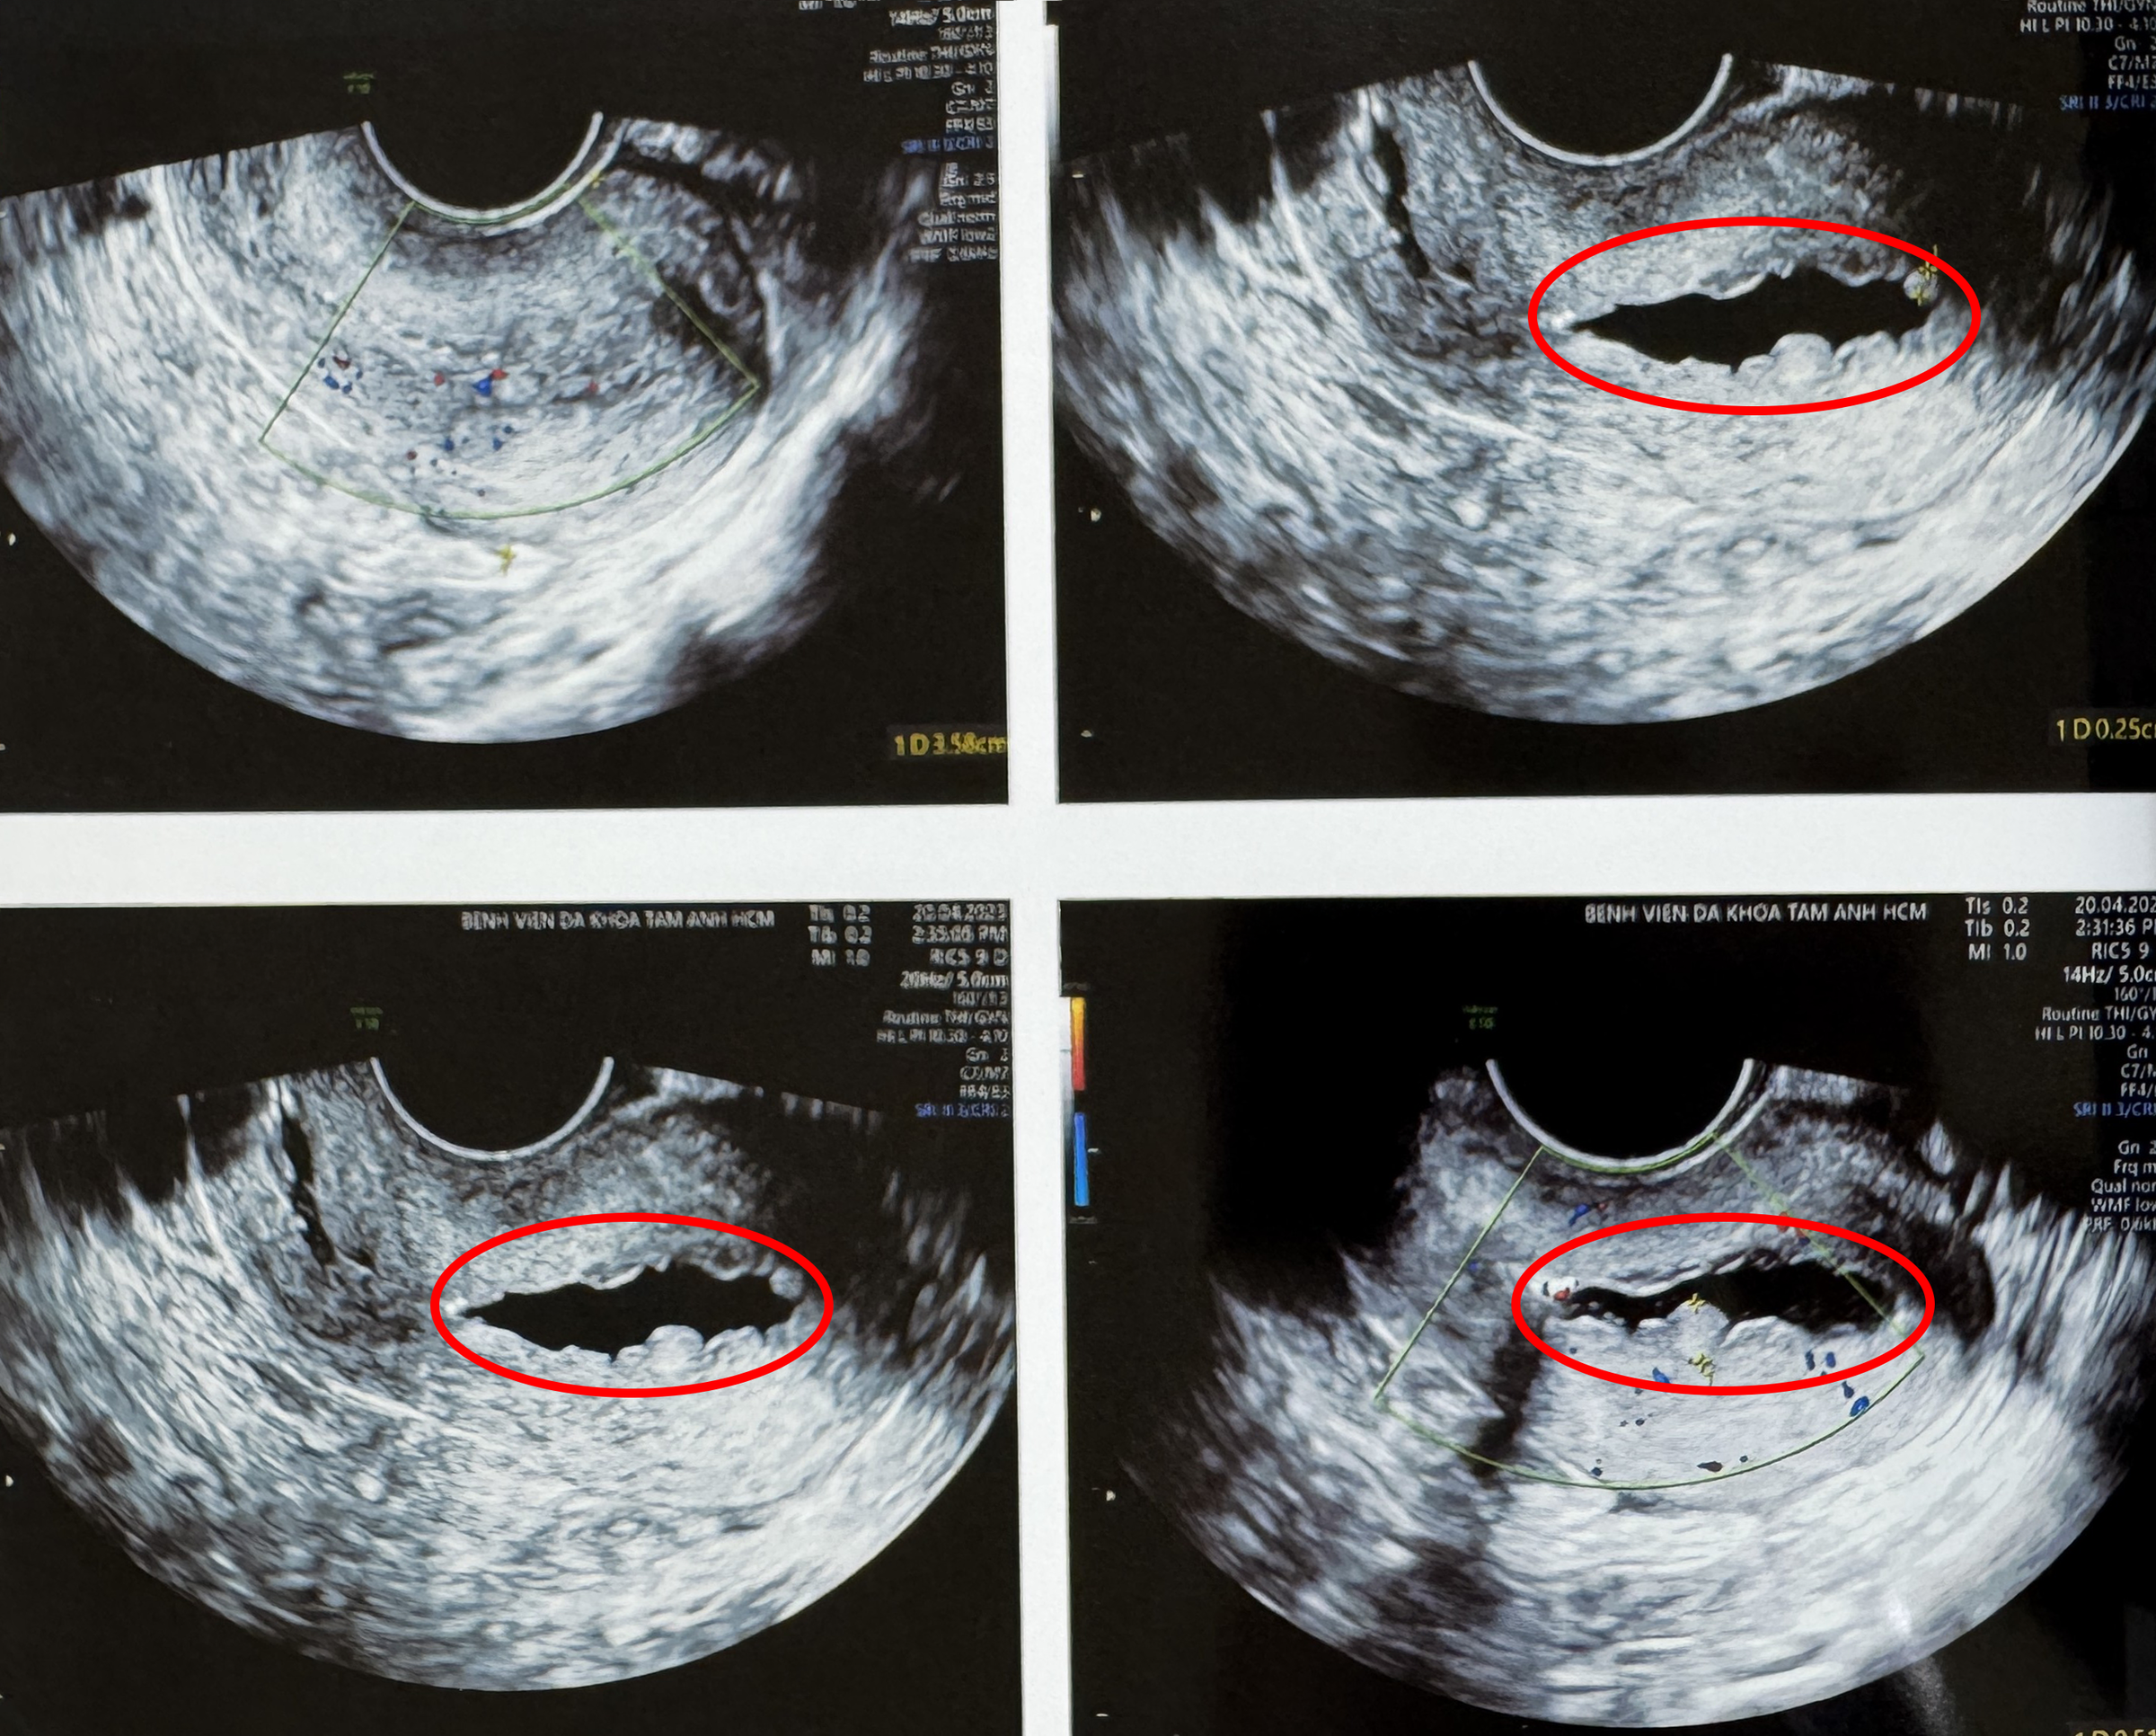

Kieu's ultrasound results show an irregular serrated uterus due to the tuberculosis bacteria. Photo: Tam Anh General Hospital

Kieu and her husband came to IVF Tam Anh TP HCM after two years of marriage without conceiving. Her husband's reproductive health was normal, but Kieu's fallopian tubes were completely blocked, with multiple lumps and thick endometrial polyps in her uterus. Doctor Vy took a biopsy and confirmed that Kieu had endometrial tuberculosis, also known as genital tuberculosis, caused by the Mycobacterium tuberculosis bacteria.